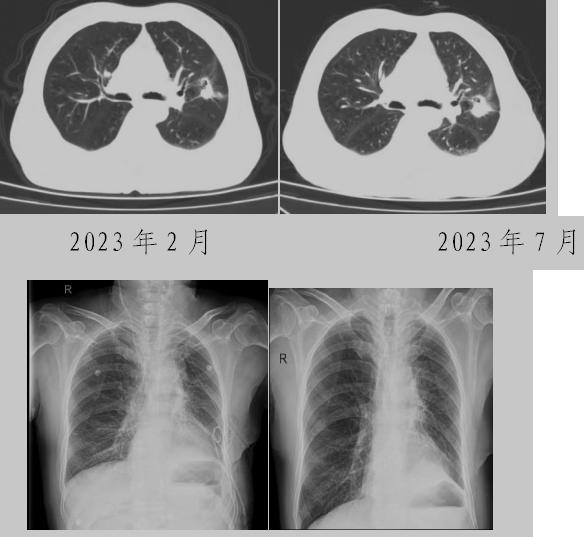

病例二:42歲的范女士,半年前體檢時(shí)發(fā)現(xiàn)雙側(cè)多發(fā)肺結(jié)節(jié),平時(shí)沒(méi)有什么不適。四個(gè)月后再次復(fù)查胸部CT,左上肺及下肺多發(fā)的磨玻璃結(jié)節(jié),其中下葉9mm的結(jié)節(jié)定為高危病灶??吹浇Y(jié)果范女士坐不住了,多方打聽慕名找到了市二院院長(zhǎng)王瑾,經(jīng)“肺結(jié)節(jié)MDT”團(tuán)隊(duì)會(huì)診后,決定手術(shù)治療。入院后,胸外科副主任醫(yī)師薛飛詳細(xì)與范女士溝通,并利用Mimics做好了術(shù)前肺部三維重建手術(shù)規(guī)劃,打消了范女士心中的顧慮。經(jīng)過(guò)前期充分準(zhǔn)備后,歷經(jīng)1小時(shí)30分,完成“胸腔鏡下左肺上葉舌段楔切及左肺下葉背段切除術(shù)”,術(shù)后病理檢查結(jié)果確診為左肺微浸潤(rùn)性腺癌。在胸外科團(tuán)隊(duì)的悉心照顧下,患者術(shù)后恢復(fù)良好,一周后順利出院。